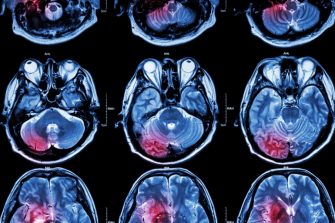

Brain Scan

Centre for Healthy Brain Ageing (CHeBA)

CHeBA is a world leader in the investigation of healthier brain ageing and better clinical care of age-related brain diseases. Their mission is to conduct innovative research and provide the empirical basis to prevent and treat Alzheimer’s disease and other dementias to achieve healthy brain ageing for all individuals.

Stroke brain scan

NeuRA

Neuroscience Research Australia (NeuRA) is an independent, not-for-profit research institute based in Sydney, Australia. As a leader in brain and nervous system research, our goal is to prevent, treat and cure brain and nervous system diseases, disorders and injuries through medical research.